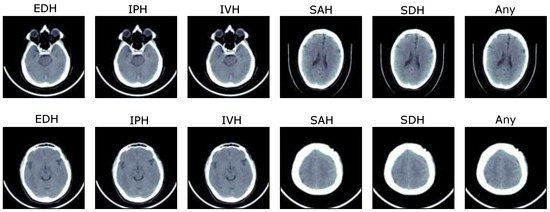

2.1.2. Multiwindowing and Adjacent Slicing